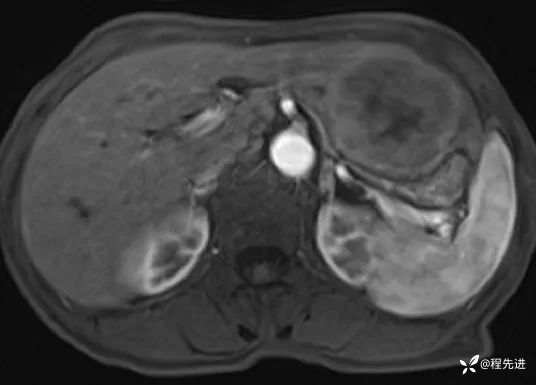

T2压脂: